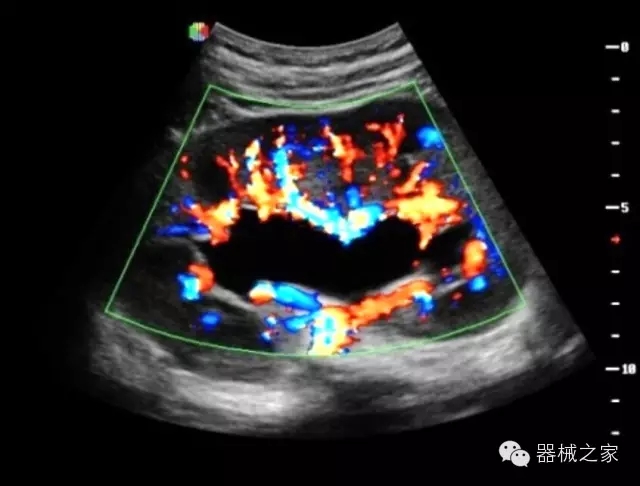

臨床圖片賞析

優(yōu)異的成像技術(shù)

·亞陣元技術(shù):獨(dú)有的亞陣元技術(shù),對(duì)獨(dú)立晶片做二次切割,減少旁瓣偽像,增加臨床診斷的準(zhǔn)確性;

·μ-Scan微米成像技術(shù):開立獨(dú)有的μ-Scan技術(shù),還原出真實(shí)細(xì)膩、層次對(duì)比優(yōu)異的二維圖像;

·智能微血流成像技術(shù):智能微血流捕捉技術(shù)可以提取出隱藏在背景噪聲中的弱血流信號(hào),大大提高低速血流的敏感性;